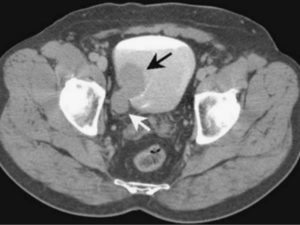

Метастазы рака мочевого пузыря

Аксиальное Т1-взвешенное изображение (а), Т2-ВИ с жироподавлением (б) у пациента с раком мочевого пузыря. Определяется мелкое объемное образование шейки левой бедренной кости (стрелки).

При внутривенном контрастном усилении (с) – Т1 c FS определяется усиление данного мелкого образования, что позволяет подтвердить вторичную, метастатическую природу данного очага, несмотря на его малые размеры.